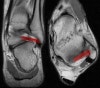

3. Posterior Talofibular ligament

Coronal (left) and axial (right) T1W images assessing the normal posterior talofibular ligament. This ligament is normally less dark than the anterior talofibular ligament.